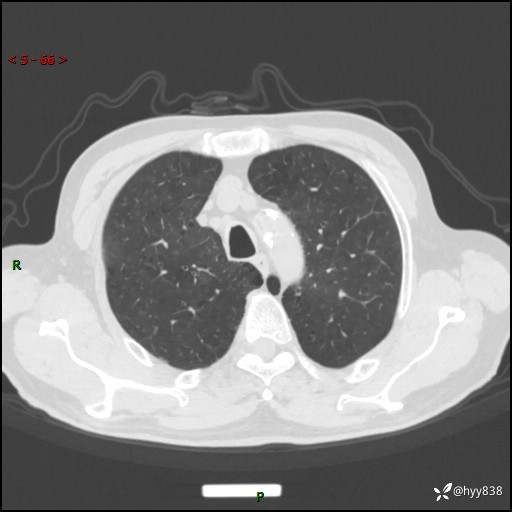

辅助检查:CT

胸部CT平扫